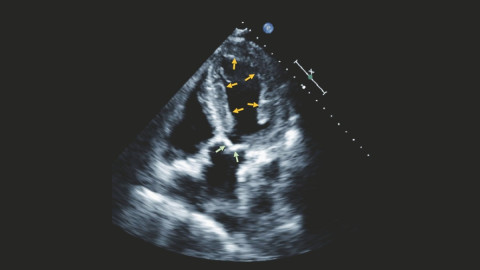

Herzbeschwerden sind das Spezialgebiet von Kardiologen und Kardiologinnen. Sie messen bestimmte Blutwerte, schreiben ein Elektrokardiogramm (EKG) und machen eine Ultraschalluntersuchung des Herzens (Echokardiografie). Allerdings ergeben sich daraus nicht immer die typischen Zeichen der Amyloidose. Unter Umständen ist die Zusammenarbeit mit Spezialisten für Seltene Erkrankungen, Humangenetikerinnen und weiteren Fachdisziplinen erforderlich.

- Magnetresonanztomografie des Herzens infrage (kardiale MRT): macht verdickte Herzwände und Proteinablagerungen sichtbar